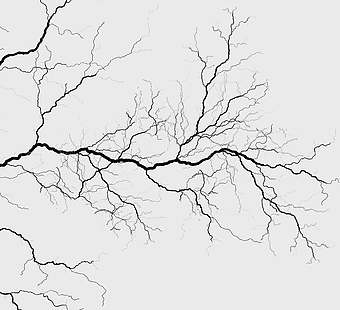

circulatory system diagram, blood vessel network, monochrome line art, pulmonary circulation illustration, vascular tree structure, anatomical line drawing, systemic venous system chart -